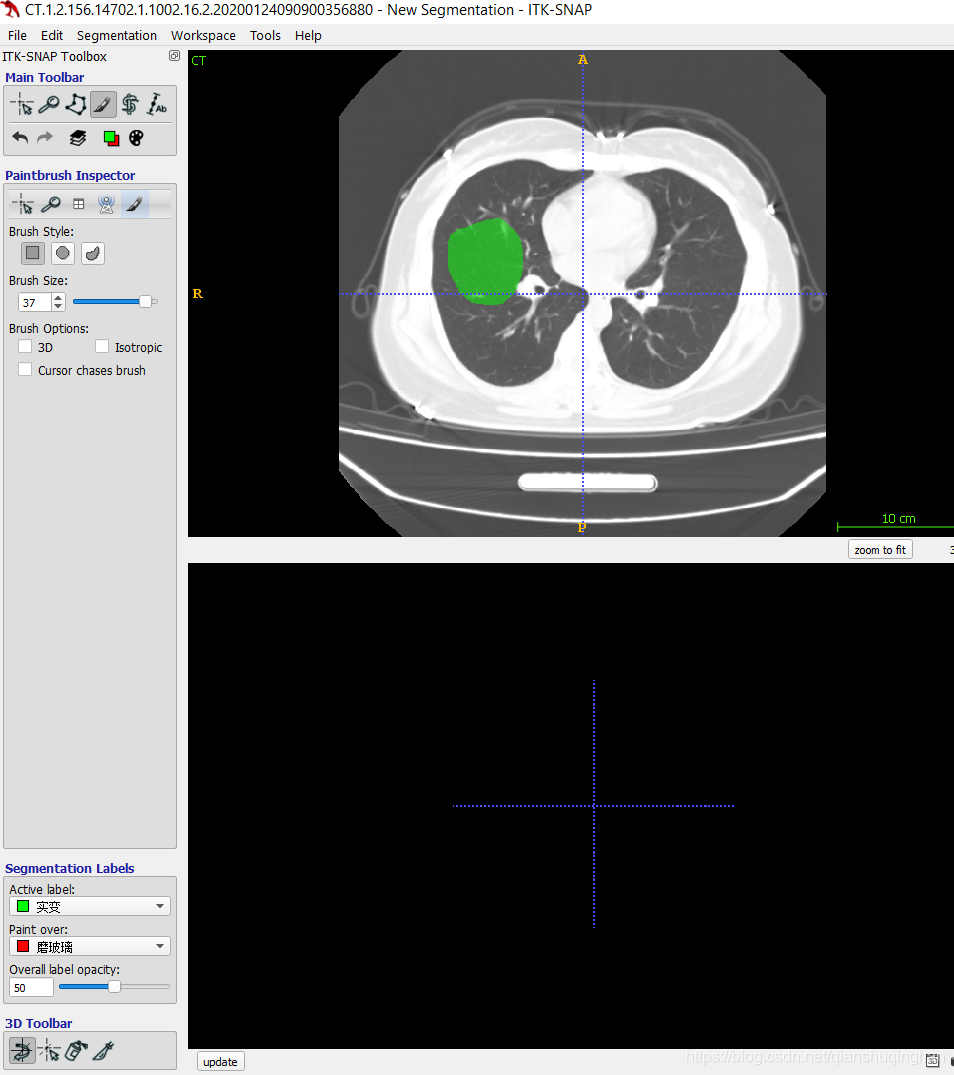

调整病灶的标签(比如,从磨玻璃 调整为实变)

如想将此标签从当前的磨玻璃改成实变,选择画刷模式,将Active label选为实变,将paint over选为磨玻璃,然后用笔刷涂抹即可修改

修改后

调整完后,切记将Active label选为你需要画的类型,将paint over恢复All labels